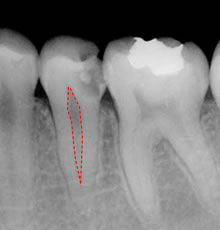

初診時のレントゲン。歯の真ん中にある空間に神経が入っています

根管充填後のレントゲン

全く違和感は無くなったので根管治療の為に削った歯冠部をコンポジットレジンで修復治療しました。

レントゲンで映っている歯の内部の白いものが詰め物です。詰め物には、ペースト状のバイオセラミクセメント(MTA)をガッタパーチャと充填しています。虫歯で削った歯の上の方の空間はコンポジットレジンと呼ばれる歯と同系色の白い詰め物、(プラスティックとセラミックの混ぜ物)を詰めて終了です。